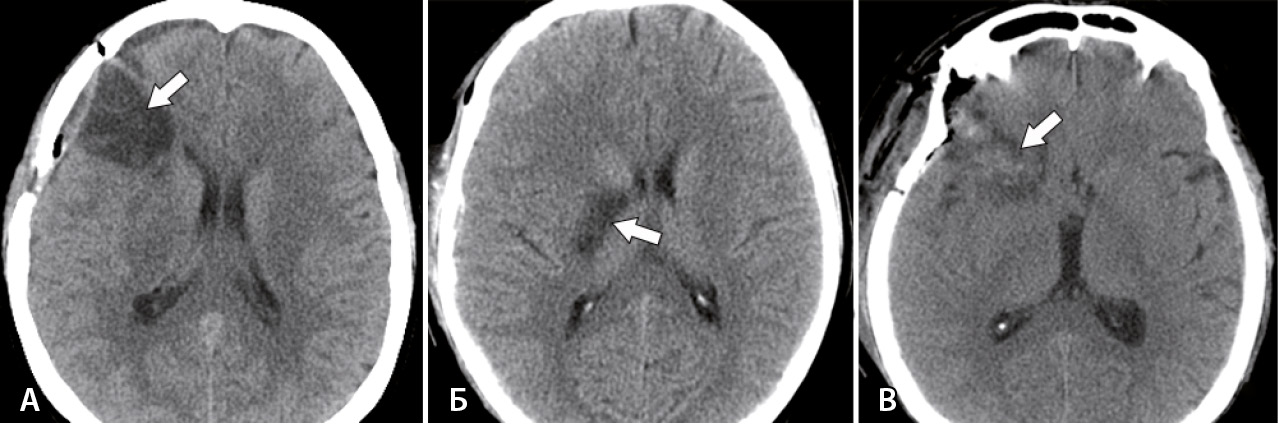

Наиболее частым послеоперационным осложнением была ишемия головного мозга, которая наблюдалась у 27 (49,1%) пациентов. Как видно из данных табл. 4, в 10 случаях (18,2%) она была связана с окклюзией на уровне М2- или М3-сегментов СМА. У этих пациентов при аксиальной компьютерной томографии отмечались гомогенные очаги пониженной плотности с четкими границами, распространяющиеся в пределах одной или нескольких долей полушария головного мозга (рис. 3A). В 9 из 10 случаев к моменту выписки у пациентов сохранялась стойкая неврологическая симптоматика. Показатель МШР на момент выписки варьировал от 1 до 5 баллов (медиана – 3 балла). Очаги ишемии в области базальных ганглиев при нарушении кровообращения в лентикулостриарных артериях отмечались в 8 (14,5%) случаях. Они имели относительно небольшие размеры и четкие границы (рис. 3Б). При этом стойкая неврологическая симптоматика к моменту выписки была только у 5 пациентов. Показатель МШР колебался от 1 до 4 баллов (медиана – 3 балла).

Рис. 3. Виды послеоперационных ишемических нарушений (стрелки): А – ишемия в бассейне лобной ветви средней мозговой артерии справа; Б – ишемия в бассейне лентикулостриарной артерии справа; В – ишемия, связанная с нарушением венозного оттока в области правой лобной доли

В 9 (16,4%) случаях отмечены гетерогенные очаги ишемии, которые имели нечеткие границы и распространение в пределах одной доли: у 6 пациентов в лобной доле и у 3 – в височной. У 4 пациентов эти очаги сопровождались вторичным геморрагическим пропитыванием (рис. 3В). Мы связали данные ишемические очаги с нарушением оттока в мостиковых венах, которые были повреждены в ходе микрохирургической операции. Доля данных нарушений среди микрохирургических операций составила 17,6%. В 7 из 9 случаев эти очаги приводили к неврологической симптоматике. У 4 пациентов симптоматика практически полностью регрессировала к выписке, и только у 3 больных с венозной ишемией к моменту выписки наблюдались стойкие неврологические симптомы. Показатель МШР на момент выписки составлял от 1 до 4 баллов (медиана – 2 балла).